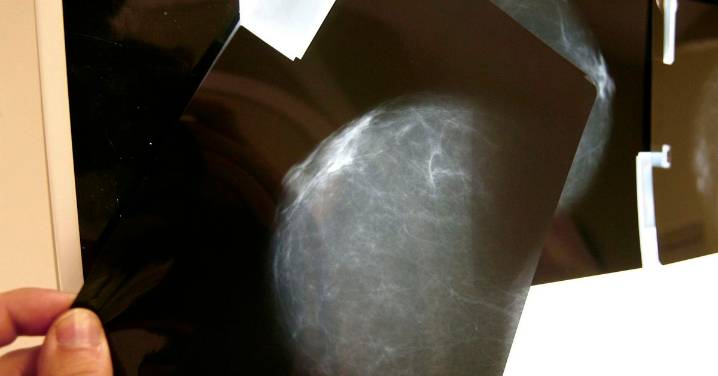

Amama tiene documentados 16 casos de pacientes de Córdoba que ya tienen cáncer de mama y que reclamarán al Servicio Andaluz de Salud (SAS) tras verse afectadas por los fallos de comunicación en los cribados. Así lo ha confirmado este martes la presidenta de la asociación, Ángela Claverol, que ha recordado que los datos ofrecidos tras la segunda reunión de la comisión de seguimiento "no cuadran ni por cantidades ni por provincias". La Junta indicó el martes que Córdoba era la única provincia andaluza sin mujeres afectadas .

Claverol ha anunciado que la entidad ha presentado ya 25 denuncias -reclamaciones patrimoniales- de mujeres de las provincias de Sevilla (15) y Jaén (diez) que han desarrollado cáncer por los fallos de comunicación en el cribado del cáncer de mama, al no ser infor